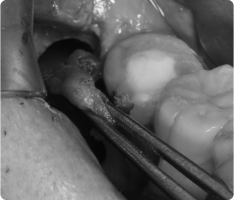

함치성 낭종은 나지 않은 치아(주로 사랑니, 송곳니) 주위에 생기는 물주머니(낭종)입니다.

치아가 잇몸 속에서 올라오지 못하고 머물면서 그 주위에 액체가 고여 발생합니다.

- 흔히 사랑니나 매복된 송곳니에서 발견됩니다.

- 크기가 커지면 주변 뼈를 흡수하거나, 옆 치아 뿌리를 밀어 손상시킬 수 있습니다.

- 대부분 통증이 없어 정기적인 X-ray 검사에서 우연히 발견되는 경우가 많습니다.

- 국소마취 후 잇몸을 열어 낭종과 함께 원인 치아를 제거합니다.

- 낭종 벽을 깨끗이 적출하여 재발을 막습니다.

- 병리검사를 통해 정확한 진단을 확인합니다.

- 작은 경우는 간단히 제거가 가능하고, 큰 경우는 단계적으로 치료하기도 합니다.